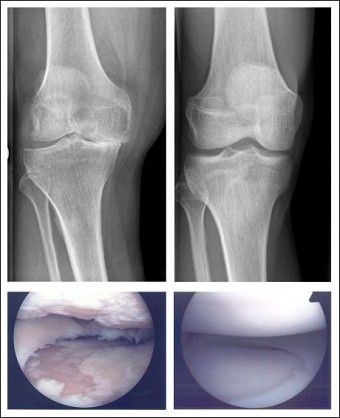

Bild 1: Röntgenbild einer

Kniegelenksarthrose

Bild 1 (anklicken zum Vergrößern): Röntgenbild einer Kniegelenksarthrose. Links eine fortgeschrittene Varus-Gonarthrose (mit einem O-Bein einhergehend): Der innere Gelenkspalt ist vollkommen zusammengesunken, das Gelenk steht nicht mehr „passend“ aufeinander, die Achse ist verschoben. Darunter ein arthroskopischer Blick in ein arthrotisches Kniegelenk: Man sieht den teilweise zerstörten Knorpel und den aufgefransten Meniskus. Rechts ein normales Kniegelenk. Man beachte den gut einsehbaren Gelenkspalt und die runden, gut zueinander passenden Gelenkflächen. Darunter ein arthroskopischer Blick in ein normales Kniegelenk: Gut erhaltener Knorpel und Meniskus.